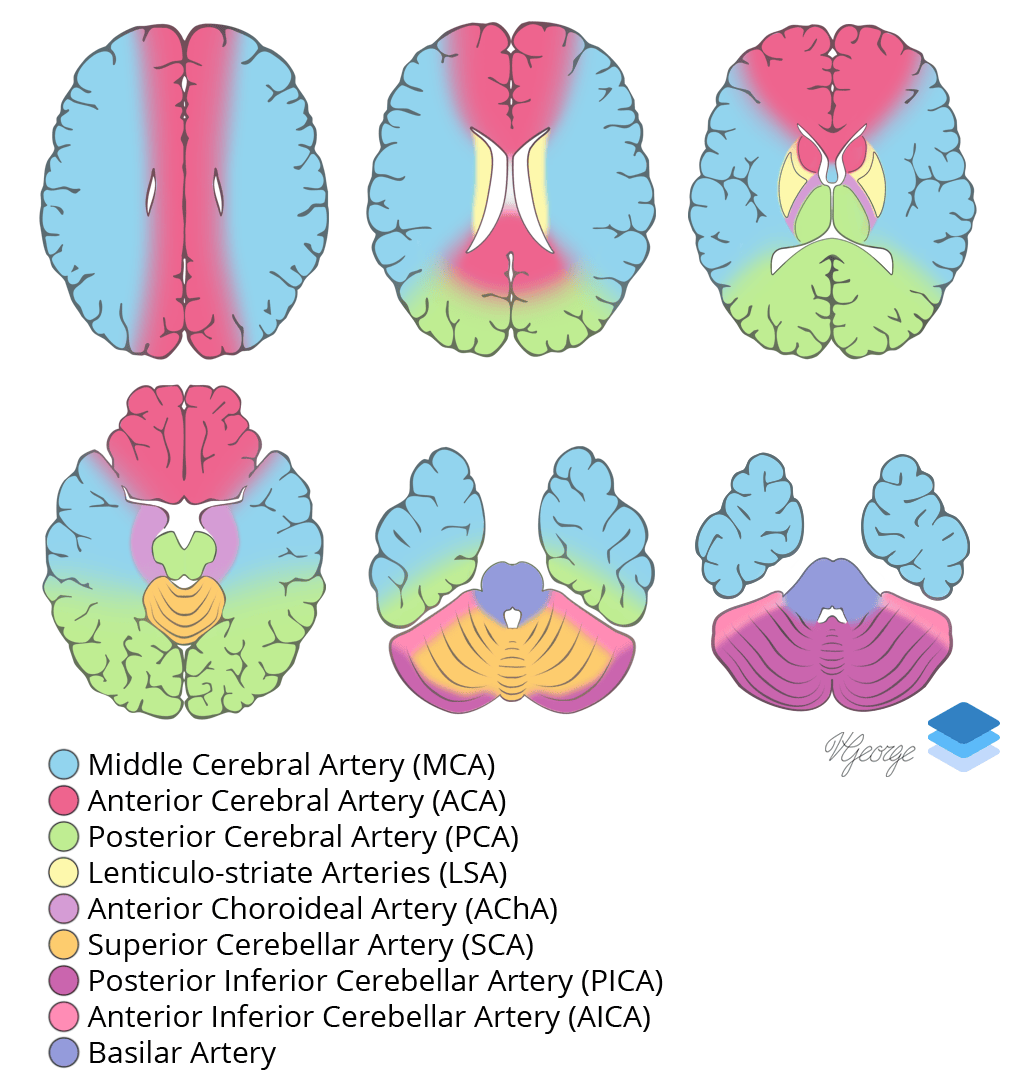

- ACA territory infarcts are much less common than MCA or PCA territory infarcts, in part because if the A1 segment is occluded, the other ACA is typically able to supply both ACA territories via the anterior communicating artery

Cross-sectional arterial territories of the brain.